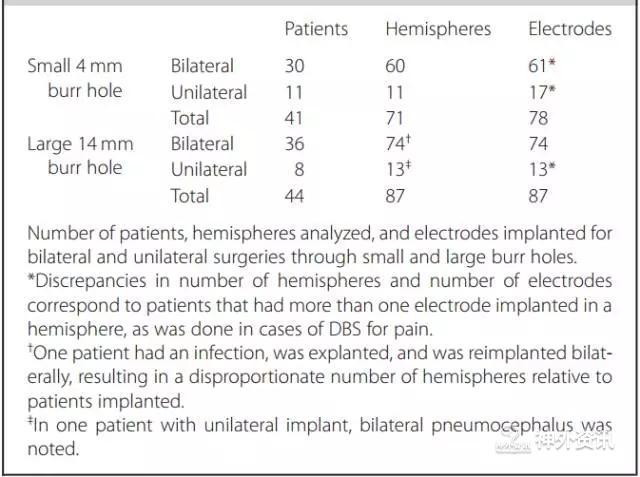

该研究共纳入85例患者,涉及158个大脑半球,植入165枚电极。根据术中骨孔大小将患者分为小骨孔组(直径4mm),涉及71个大脑半球;大骨孔组(直径14mm),涉及87个大脑半球(表1)。通过术后即刻复查CT平扫图像计算颅内积气体积(图1),对比两组患者“骨孔侧大脑半球前方的颅内积气量”是否具有统计学差异。

表1. 两组患者的一般资料。

数据分析发现,两组患者的年龄未见明显差异(P=0.73)。85例患者总体平均“骨孔侧大脑半球前方的颅内积气量”为12.22±8.58cm3;其中,小骨孔组为12.84±9.79cm3,大骨孔组为11.70±7.46cm3,两组差异无统计学意义(P=0.42)。对双侧DBS手术的患者进行亚组分析,对比“颅内积气总量”也未见统计学差异。颅内积气量与手术时长无显著相关性(R=0.027,P=0.81),与疾病类型和靶点选择无关(P值分别为0.86和0.6)。